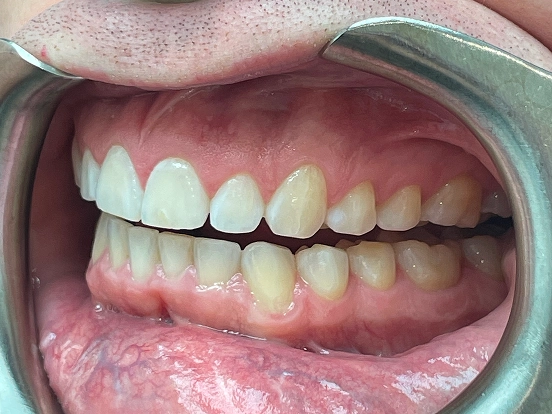

Braces EJ

EJ’s braces journey demonstrates how traditional orthodontics can deliver a complete and lasting smile transformation. The braces effectively corrected spacing and bite issues, leaving behind a perfectly straight, radiant smile that reflects months of dedication.